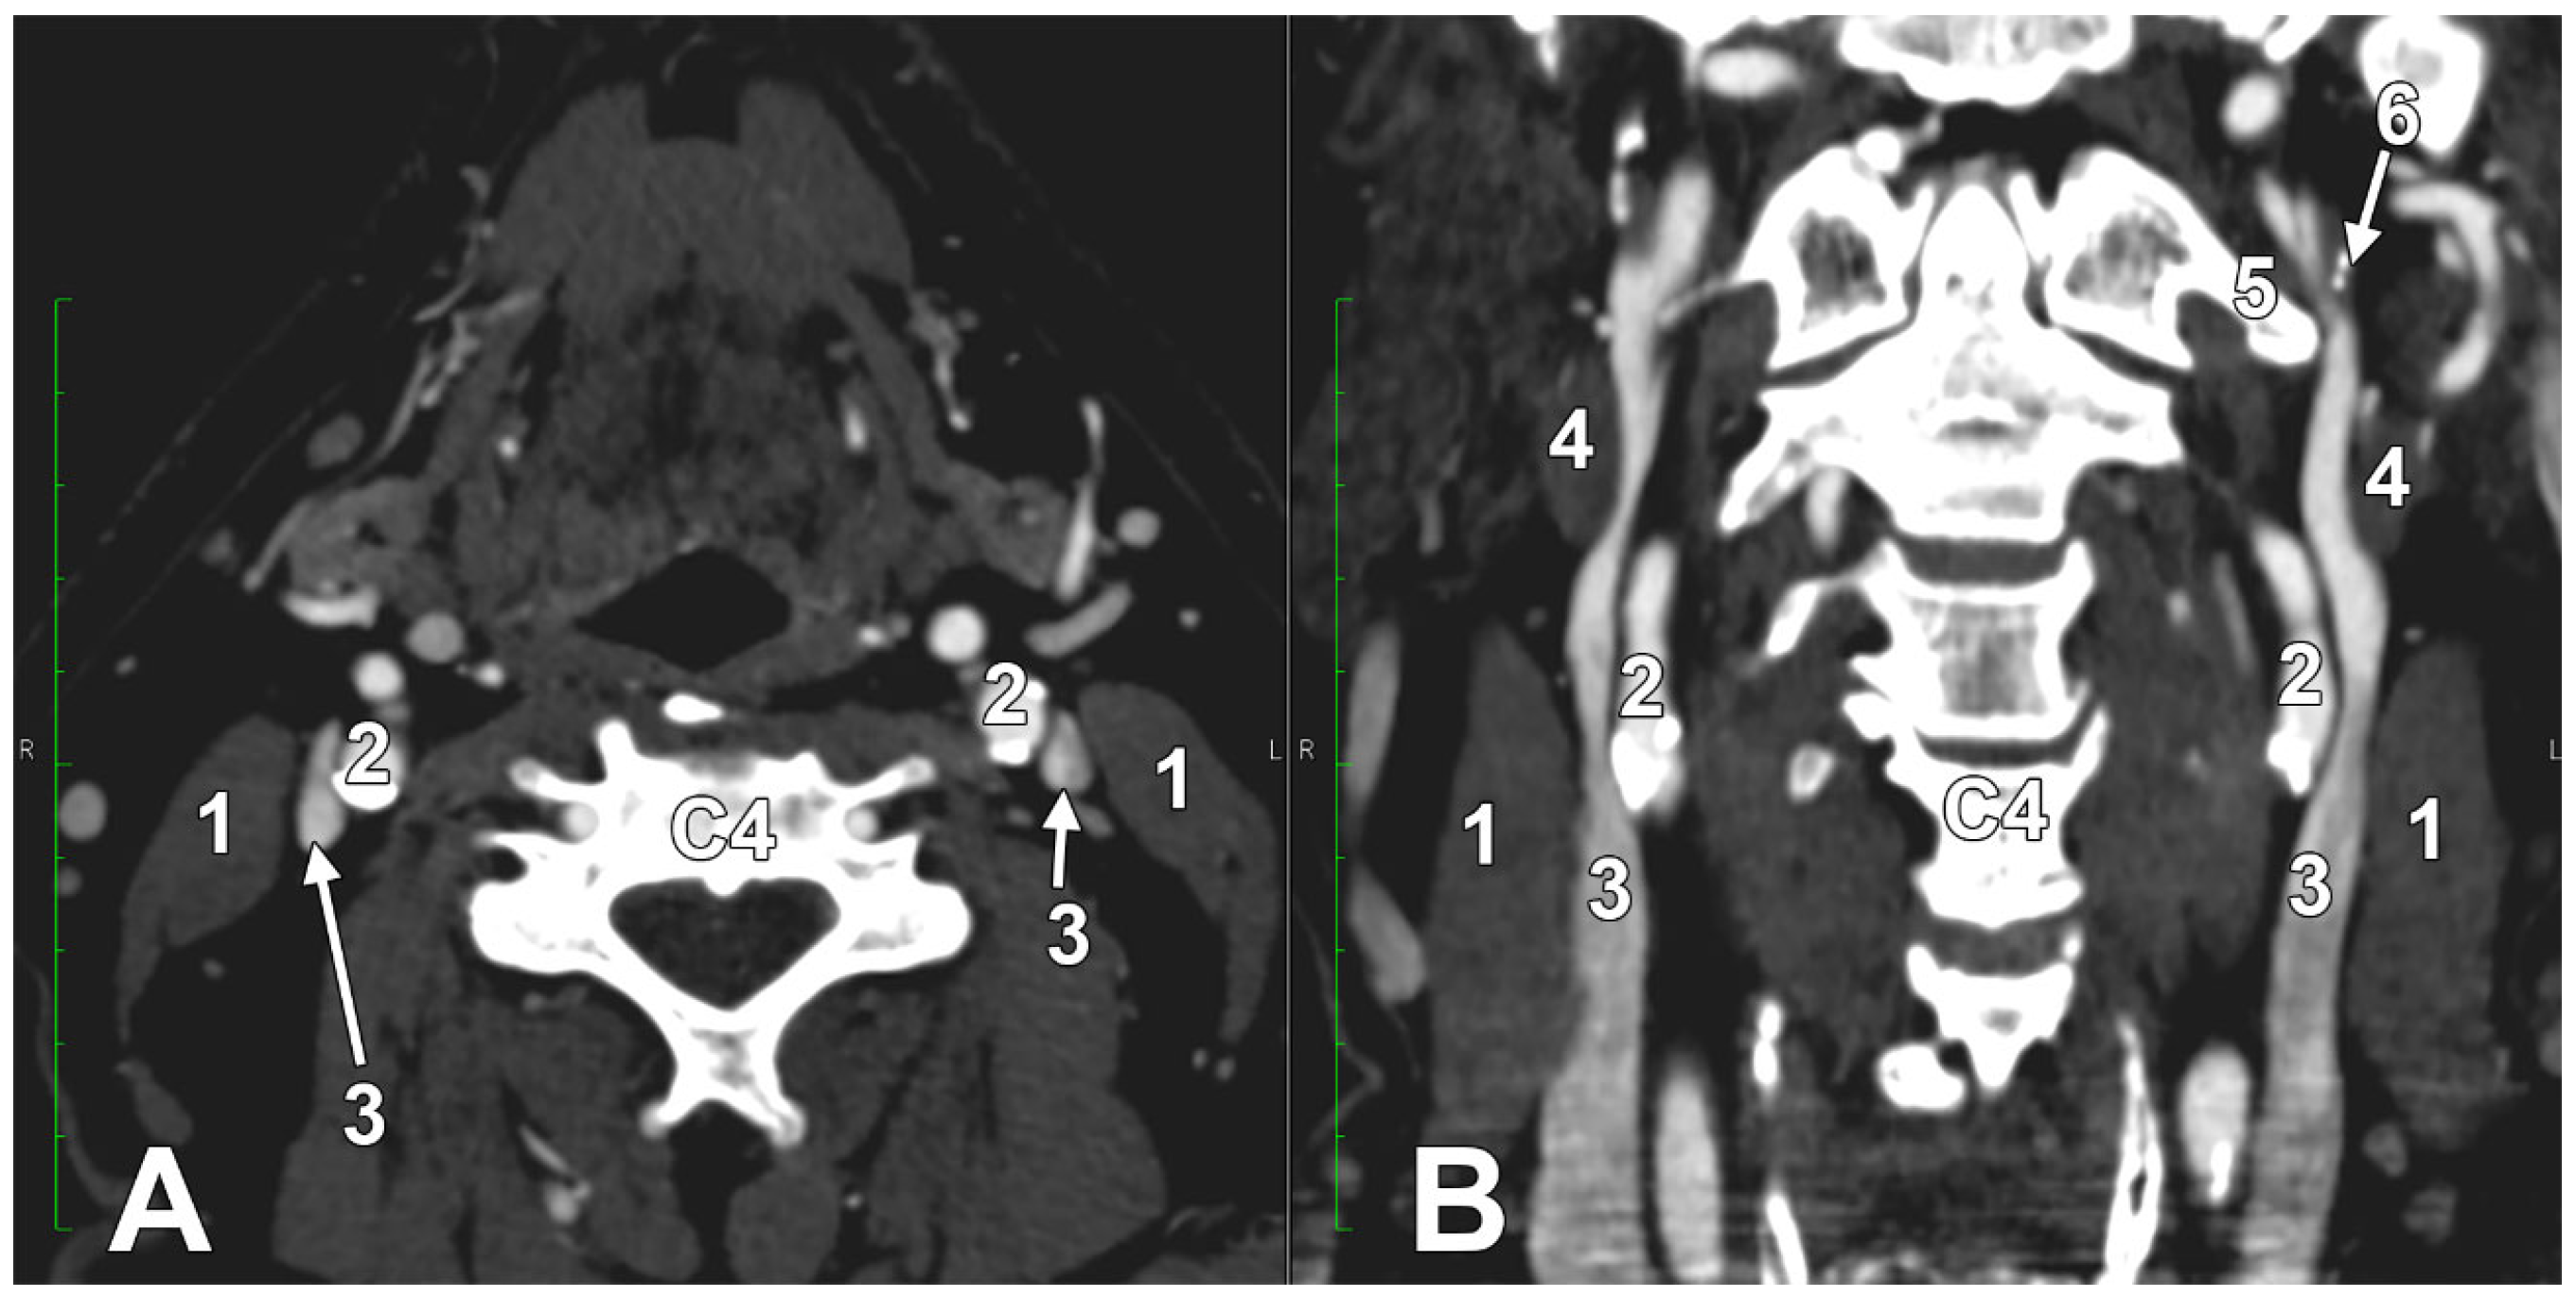

Cannulation of the right IJV is preferable to the left IJV, but when the right IJV is not available for central venous access, the left IJV may be used [2,50,199]. In such cases, it is advisable to document whether the targeted IJV is anatomically compressed. Rotation or extension of the head does not significantly change the size of the IJV [17]. Variations in position and the relationship between the IJV and the carotid arteries may lead to inadvertent artery puncture, which could be disastrous during central venous access [18]. As it descends in the neck, the IJV gradually moves from the lateral side of the CCA to anterior to it, so the percentage overlap of the IJV and CCA gradually increases [18]. Compared with the left side at the same transverse level, the distance between the CCA and the IJV is wider on the right side, and the right IJV is wider [18]. In 11/200 patients, the IJV was found medial to the CCA at one or more transverse scan levels [18]. The angle between the IJV and CCA was significantly smaller in elderly patients [18]. An imaging study found different IJV-to-CCA relations: the IJV was lateral to the CCA in 85.2% of cases, anterior to it in 12.5%, medial to it in 1.1%, and posterior to it in 1.1% [199]. In a different study, the IJV was found anterior and lateral to the CCA in 92% of cases, which corresponds to the typical anatomical descriptions [200].

A right dominant IJV is presented in Figure 11. One may observe that the IJV course, as related to the carotid axis, is bilaterally asymmetrical; the left IJV is lateral to the carotid axis, while the right IJV is posterolateral to the carotid axis. Seemingly, the bilateral symmetry of the IJV/carotid topography was consistently overlooked in previous studies [199]. An ultrasonographic study on 80 critically ill patients found that in 62.5% of cases, asymmetric IJVs [44]. The right IJV was dominant in 68% of cases, and the left IJV in 32% [44]. The IJVs were studied using transverse sections, 15 mm above the cricoid cartilage [44].